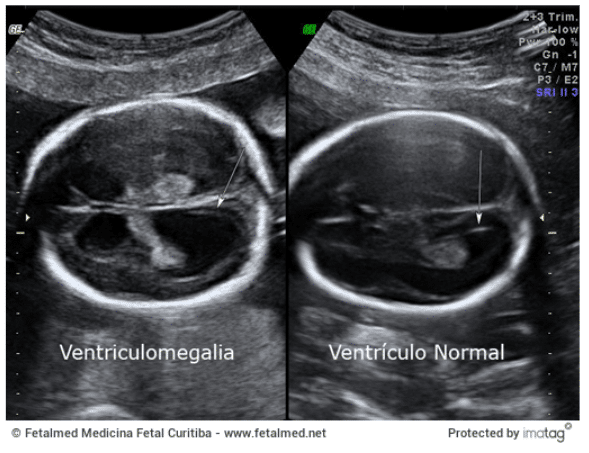

Ventriculomegalia

Dilatação dos ventrículos laterais acima de 10 mm pode indicar hidrocefalia ou infecções congênitas.

Por exemplo, o aumento do tamanho dos ventrículos cerebrais, conhecido como ventriculomegalia, é considerado um achado inespecífico que pode indicar a presença de alterações no sistema nervoso central ou em outros sistemas orgânicos.